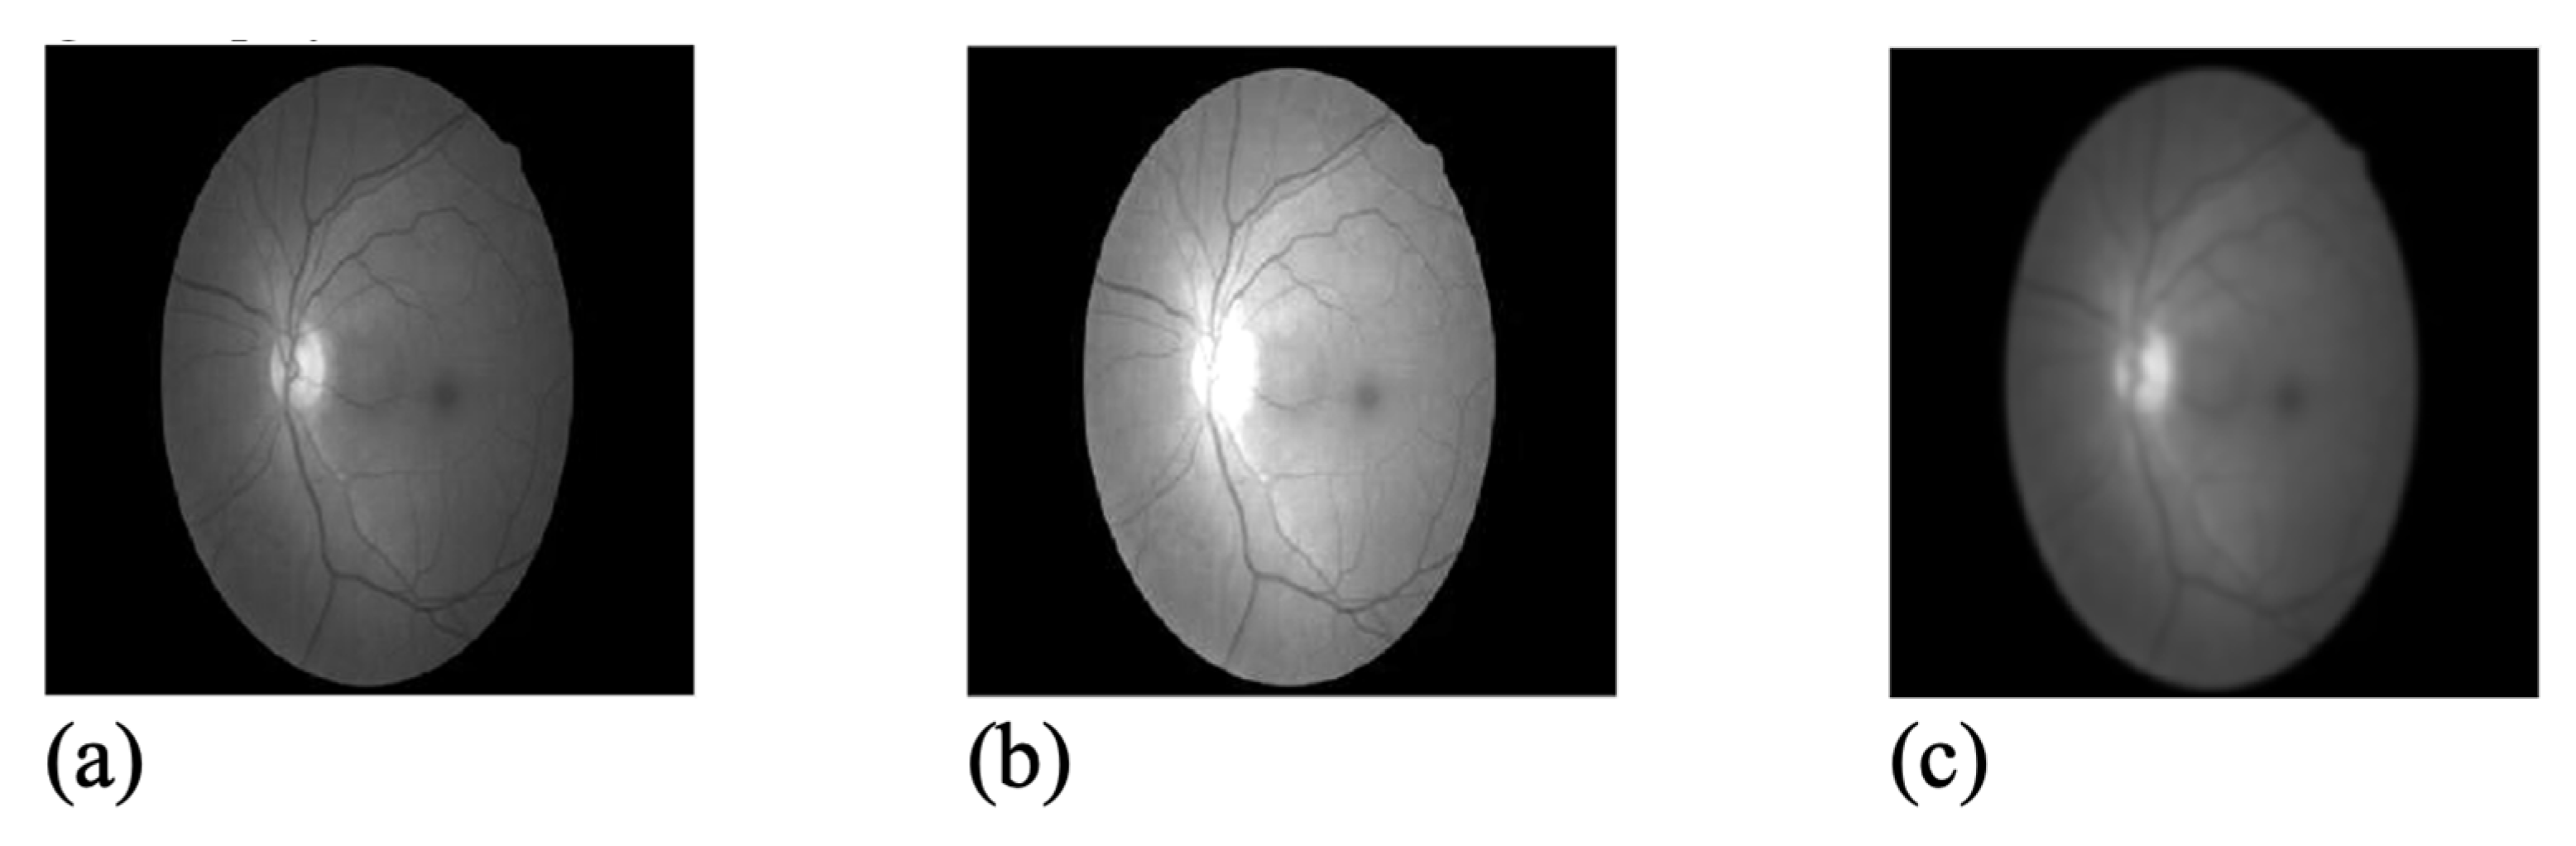

To standardize images and create appropriate contrast and brightness conditions, among other things, the histogram normalization method is used to improve the quality of retina images. This method improves image resolution by evenly distributing different intensities of pixel values. After improving the quality of retinal images, normalization of the histogram causes a Gaussian filter to be used to remove noise and smooth it. Some types of noise in the image are removed with the help of this filter, and the image loses some of its edges by losing some high frequencies, preparing the image for the next step, which is the application of Gabor filters [14]. Figure 1 shows the image of the retinal green channel, along with the contrast-enhanced image and the smoother image with the Gaussian filter.

Figure 1.

(a) The green retinal channel, (b) result of contrast improvement, and (c) result of applying Gaussian filter for smoothing the image.